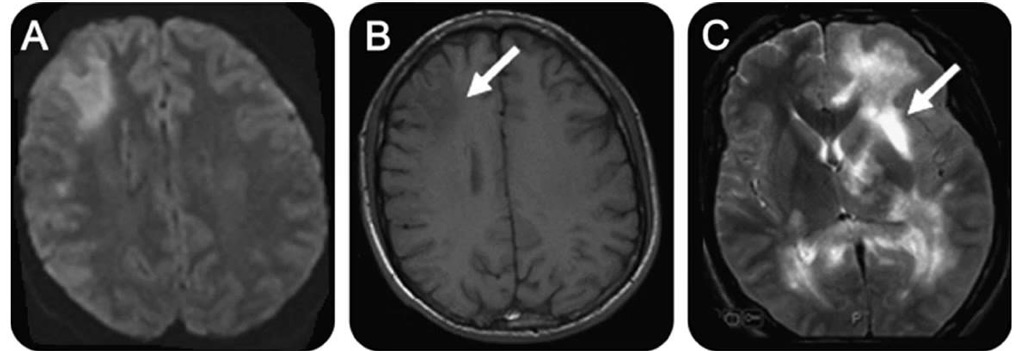

На МРТ круглые или овальные гиперинтенсивные очаги демиелинизации чаще всего выявляются в белом веществе под корковым слоем, вокруг желудочков мозга (перивентрикулярно). Они распределены диффузно и имеют разные размеры — от нескольких миллиметров до 2-3 см. Для уточнения времени появления очагов используется контрастное усиление: более «молодые» участки демиелинизации лучше накапливают контрастное вещество по сравнению с теми, которые существуют длительное время.

Заболевание обычно затрагивает несколько отделов нервной системы одновременно, включая головной и спинной мозг. Одной из характерных особенностей является наличие на МРТ бляшек различного возраста — от свежих до склерозированных. Это свидетельствует о хроническом воспалительном процессе и объясняет разнообразие симптомов, которые могут меняться по мере прогрессирования демиелинизации.